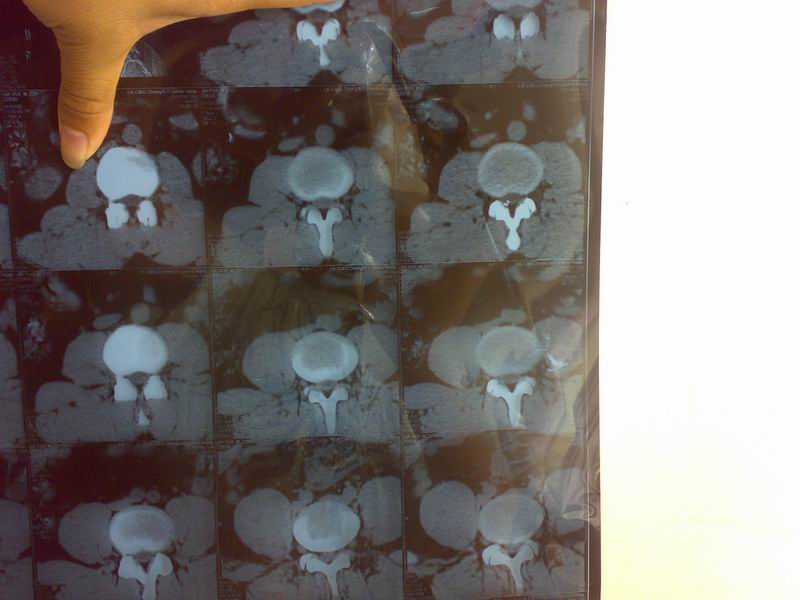

男 22岁 左边腰痛 左腿从臀部到脚都有疼痛 有是发麻

[腰部ct]l2至s1间盘螺旋ct平扫  希望帮看看是什么病 还有怎么治疗

头像模糊,应该是腰4.5椎间盘中央偏左侧形突出。比较常见牵引加按摩半月,看能好转不能,最好手术

椎间盘突出,中央型。哪个椎间盘搞不清楚。

l4-5椎间盘后突出,右侧椎小关节退行性骨质增生

腰椎间盘(腰4/5椎间盘?)突出(后外侧型)。

没定位像,不好确定是那上节椎间盘,像是腰4--5椎间盘突出(左旁中央型)伴椎管及侧隐窝狭窄,首先保守治疗四周如一理疗\\针灸\\推拿\\按摩\\牵引等,如无效可选择手术,常规外科手术或介入治疗(经皮椎间盘旋切术\\臭氧治疗\\激光治疗\\胶原酶注射等.)